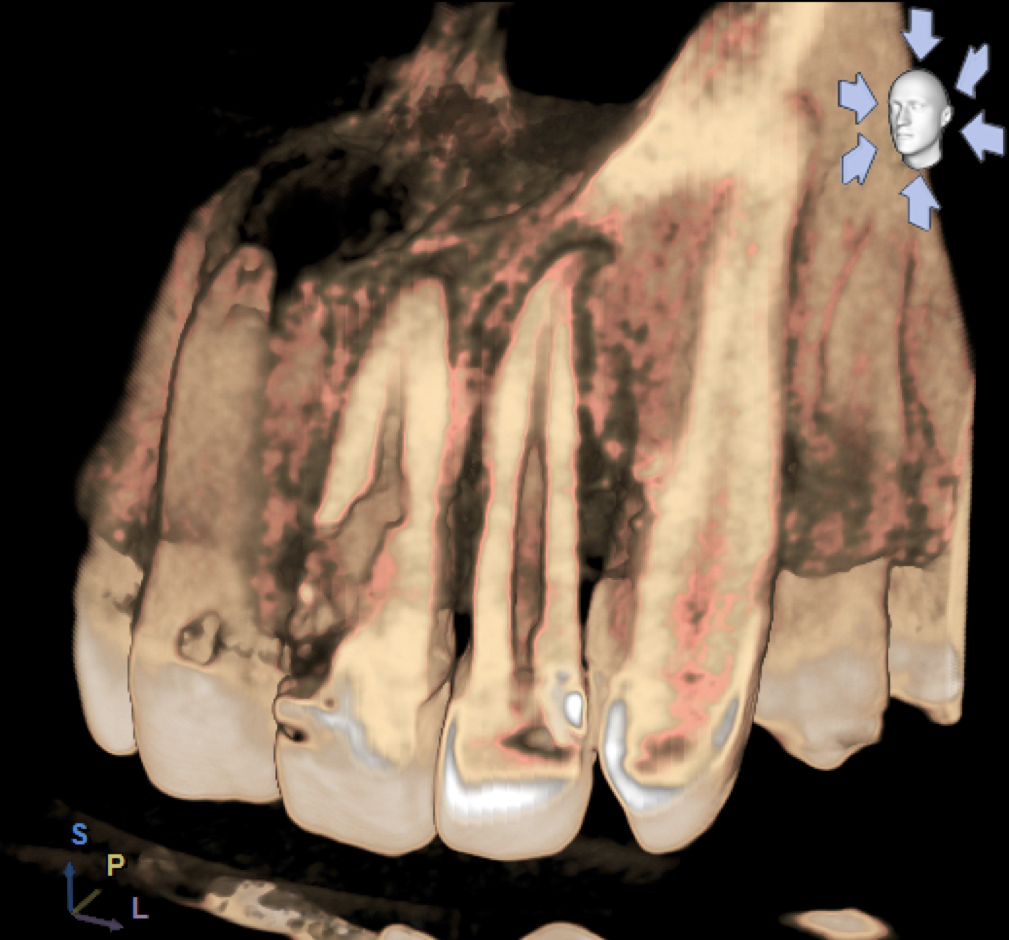

«L’imaging radiografico è fondamentale: dopo la raccolta dei dati anamnestici e un’accurata visita, il primo step è la radiografia periapicale eseguita con la tecnica dei raggi paralleli (centratori). Non sempre, tuttavia, questo esame consente di distinguere tra riassorbimento interno ed esterno; per questo è utile una seconda radiografia, con diversa inclinazione, che grazie alla sproiezione delle immagini può aiutare a chiarire il tipo di riassorbimento. Oggi però sappiamo che l’immagine bidimensionale presenta molti limiti; per questa ragione, le principali linee guida internazionali (AAE-American Association of Endodontists ed ESE-European Society of Endodontology) raccomandano un esame di secondo livello come la CBCT (FOV piccolo, alta risoluzione). Questo consente una diagnosi precisa, informazioni sulla reale estensione del processo distruttivo e, di conseguenza, un piano di trattamento più accurato».

Dal punto di vista biologico, i riassorbimenti derivano dall’attivazione di cellule clastiche capaci di degradare dentina e cemento, stimolate da fattori infiammatori o traumatici. «Le cause più comuni sono traumi, movimenti ortodontici, scaling e carie, ma talvolta il processo decorre del tutto senza sintomi. Clinicamente, i riassorbimenti radicolari possono restare occulti a lungo e venire diagnosticati solo con indagini radiografiche o, più recentemente, con CBCT, che ha migliorato la comprensione di localizzazione ed estensione del difetto, distinguendo chiaramente tra quadri interni ed esterni, distinzione fondamentale per strategie e prognosi».

Per questo oggi si raccomanda una valutazione accurata dell’estensione del riassorbimento con CBCT, l’uso di sistemi ottici ingrandenti, irrigazioni attivate e materiali bioceramici ad alta biocompatibilità e adattamento marginale.